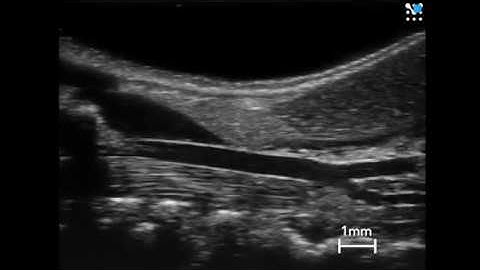

SD IEEE MATLAB ROBUST CAROTID ARTERY RECOGNITION IN LONGITUDINAL B-MODE ULTRASOUND IMAGES